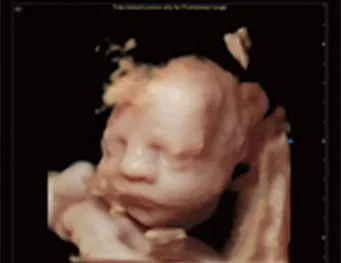

SonoAI - OB

● Software inteligente para OB, herramientas de medición precisas y de alta eficiencia

● Medir automáticamente: BPD, HC, AC, FL, NT

● Un paso para obtener el resultado